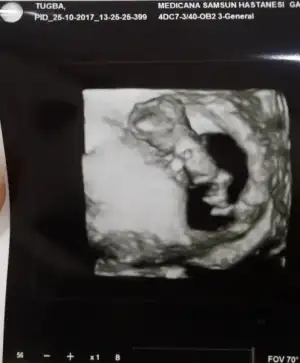

ekteki de benim bebeğim.doktor şimdilik % 51 erkek diye cinsiyeti söyledi :KK48: sizce nasıl ? benim yaşım 43 olunca ikili tarama testine girdim ama ultrasonda bebeğe bakıldı kandaise yaş itibariyle yüksek risk çıkacağı için gerek görmedi doktorum.özel hastaneye gidiyorum.ama benden kontrol amaçlı fetus dna testi yaptıralım dedi.kandan bakılıyor.1600 tl. ücreti.benim tüp bebek olduğu için embriyo genetiğe gitti bahçeci fulya da sağlıklı embriyo olduğu % 99. yanılma payı % 1.bakalım tüp bebek doktoruma yazıp soracağım whatsappdan.eğer o da yaptır derse devlet hastanelerinin genetik tanı bölümü bakıyor bu teste.numune hastanesine gitsem mi diyorum sofiarya sofiarya senin bir bilgin var mı ? biz tüp bebekte o kadar paralar harcadık ki şu an 1.600 tl. artık vere.bileceğim bir rakam değil.fetüs dna testi yaptıracak olan araştırma içinde olup ücretleri bilen var mı ankaradayım bu arada.

Maşallah ne kadar net gözükmüş. :nazar: